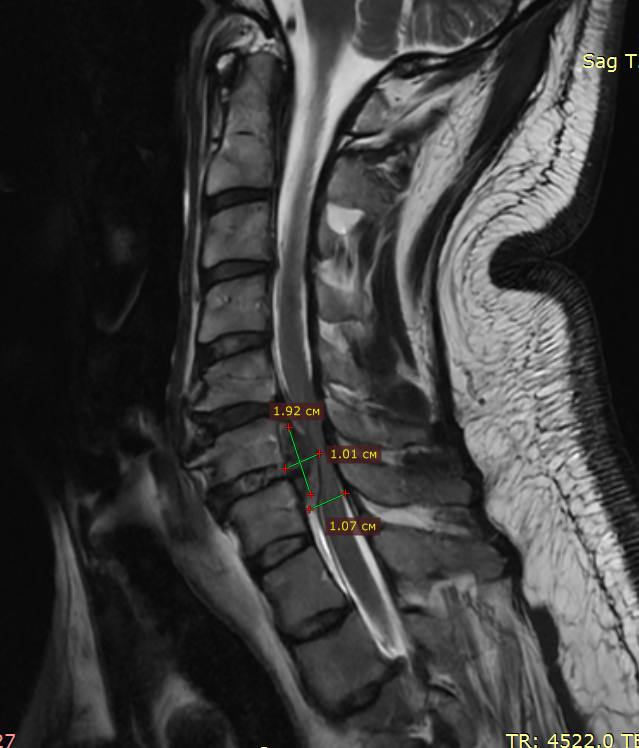

«Неврологический дефицит, слабость в руках и ногах были такой степени, что человек не мог сам передвигаться и не мог сам пищу принимать без помощи. Из-за грыжи межпозвонковый диск полностью мигрировал в позвоночный канал, образовалась гигантская грыжа в шейном отделе на уровне С5-С6 позвонков. Размер грыжи составил около 2×1 см, но нужно понимать, что сама ёмкость канала на этом уровне составляет чуть больше сантиметра. Произошло сильное сдавление спинного мозга и его корешков, нервной ткани, что требовало срочного хирургического лечения в специализированной операционной», — объяснил к.м.н., заведующий отделением нейроортопедии Алексей Пелеганчук.